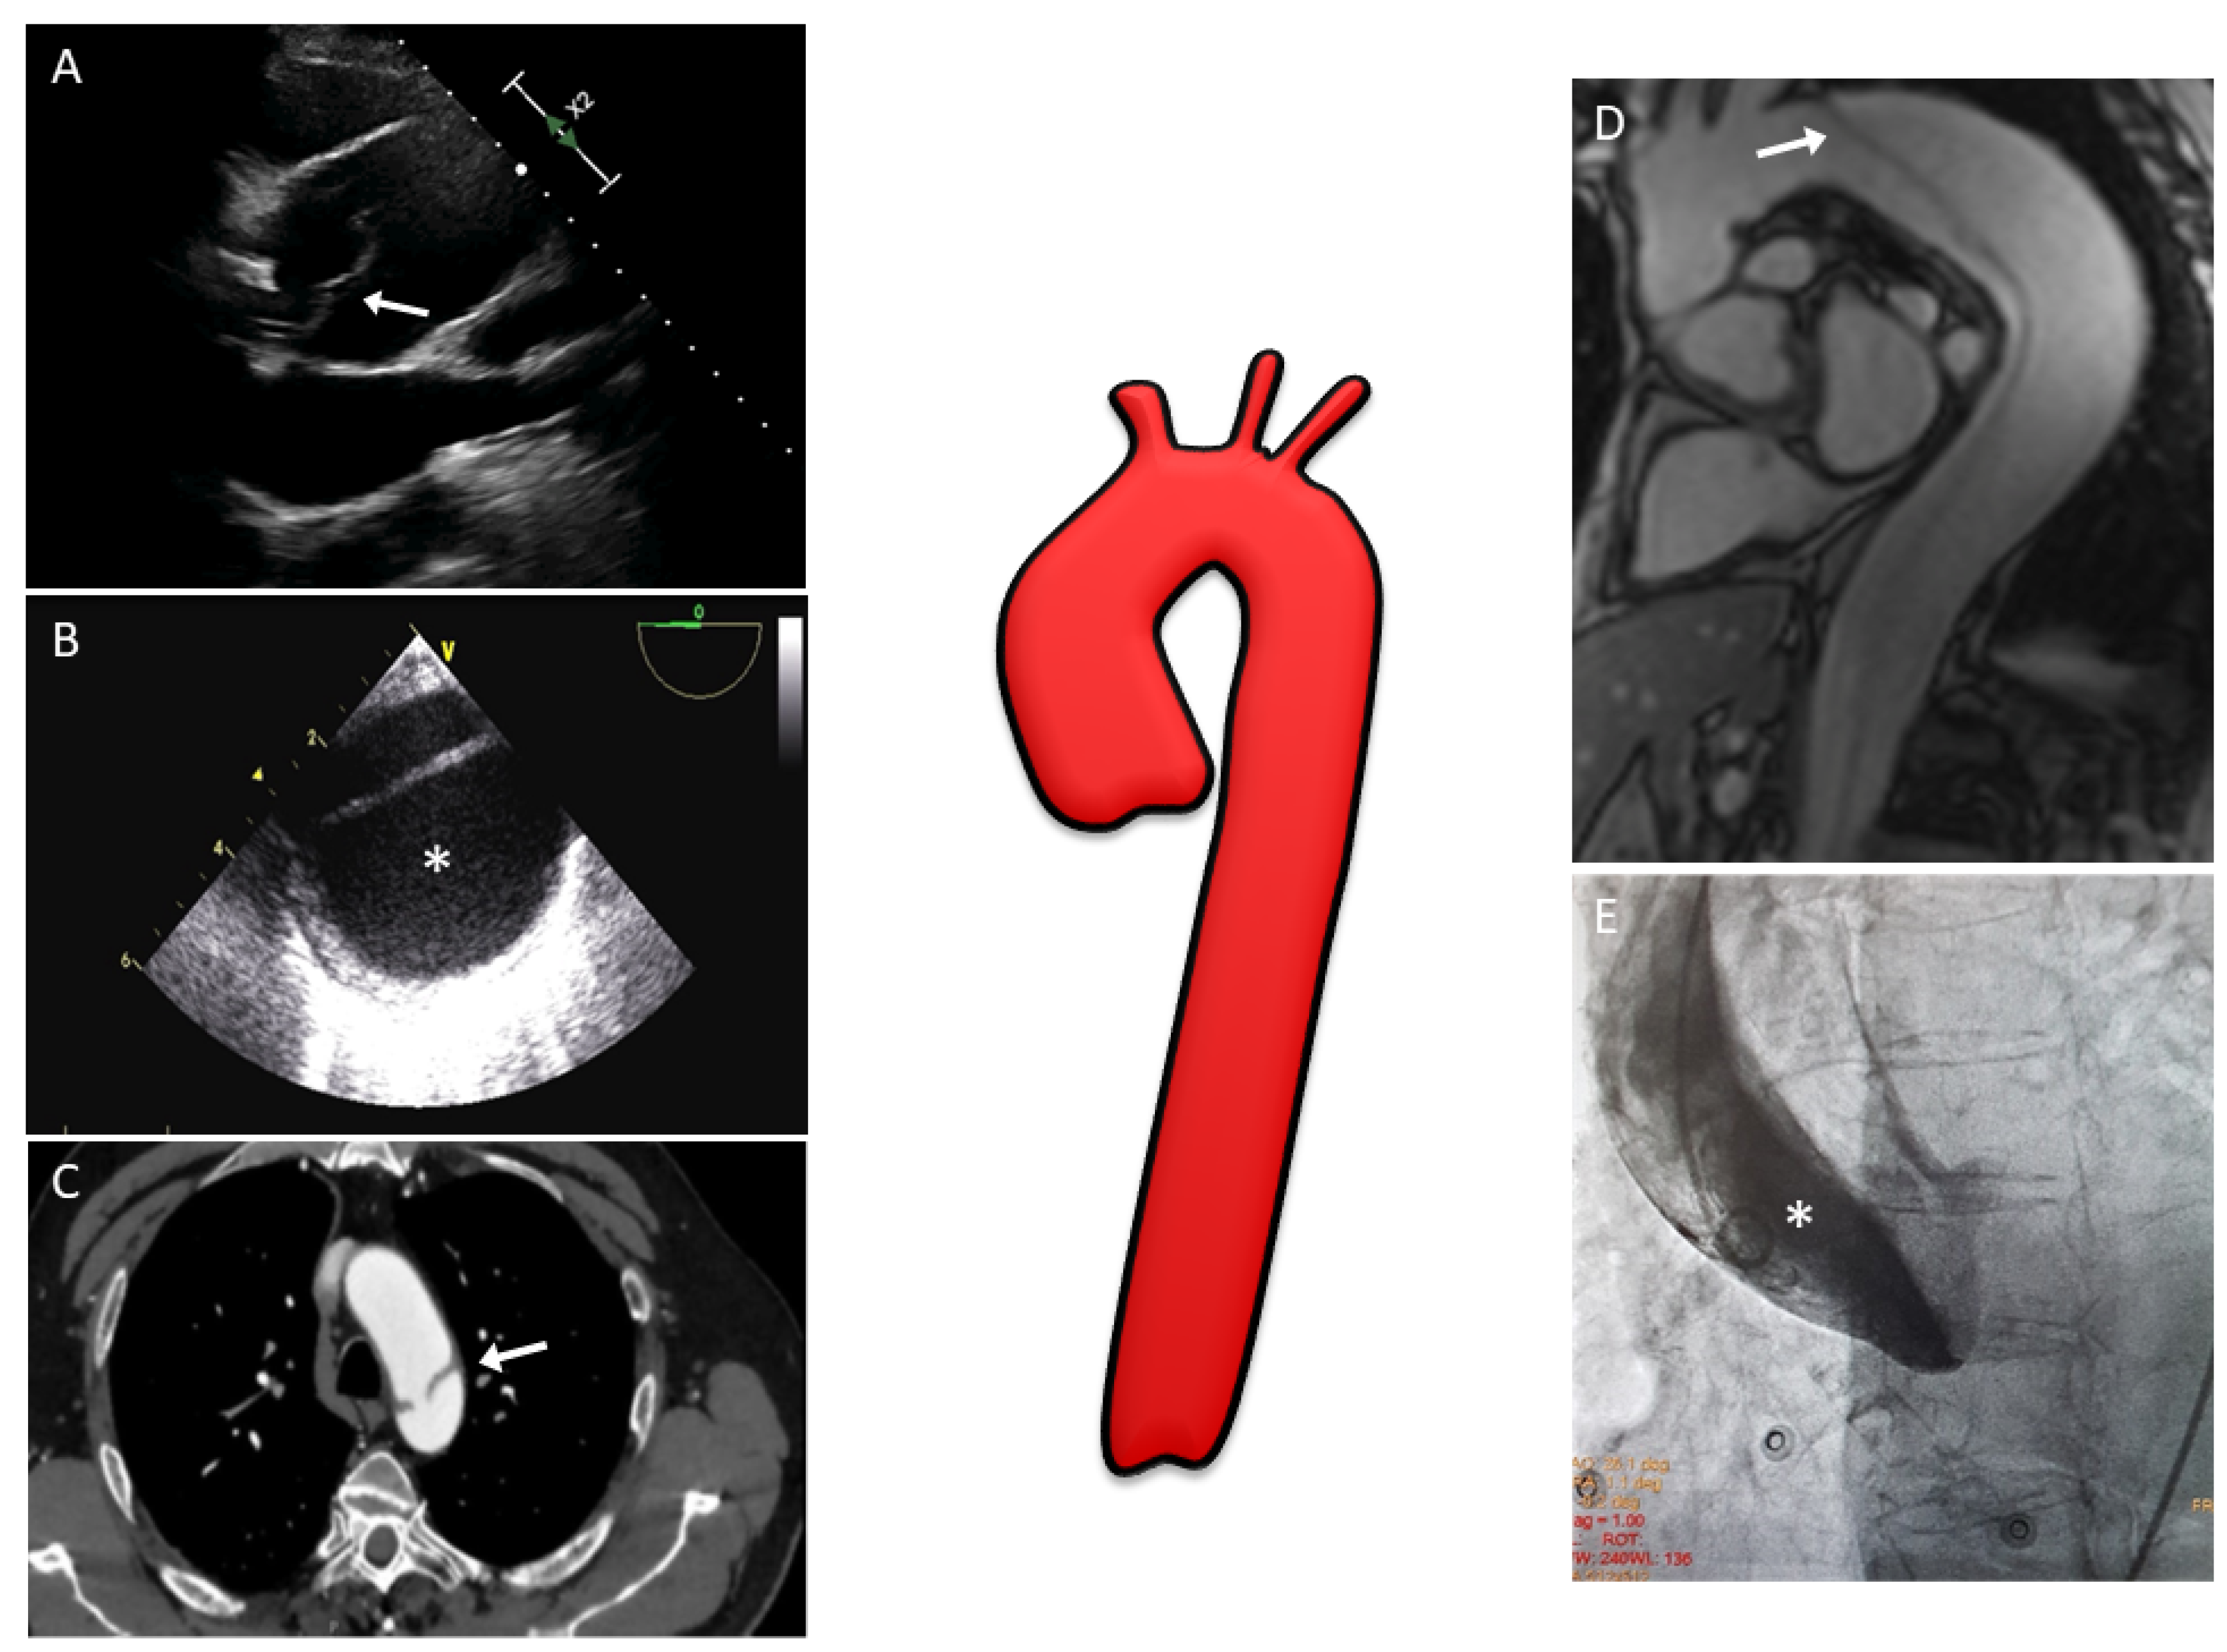

Aortic Dissection and Other Acute Aortic Syndromes Diagnostic Imaging Aortic Dissection Mcq Questions Click the card to flip 👆. Aortic aneurysm etiology & pathophysiology. study with quizlet and memorize flashcards containing terms like which patient is at highest risk for developing an aortic. skip to main content. 1.in adults, aortic diameter at the origin is approximately ? aortic dissection is a condition that results from a tear in the innermost. Aortic Dissection Mcq Questions.

Diagnostics Free FullText The Role of Multimodality Imaging Aortic Dissection Mcq Questions Aortic aneurysm etiology & pathophysiology. Click the card to flip 👆. Health topics healthy living symptoms emergencies. 1.in adults, aortic diameter at the origin is approximately ? see all quizzes of diseases of the aorta at here: Health topics healthy living symptoms emergencies resources news about. aortic dissection is a condition that results from a tear in the. Aortic Dissection Mcq Questions.